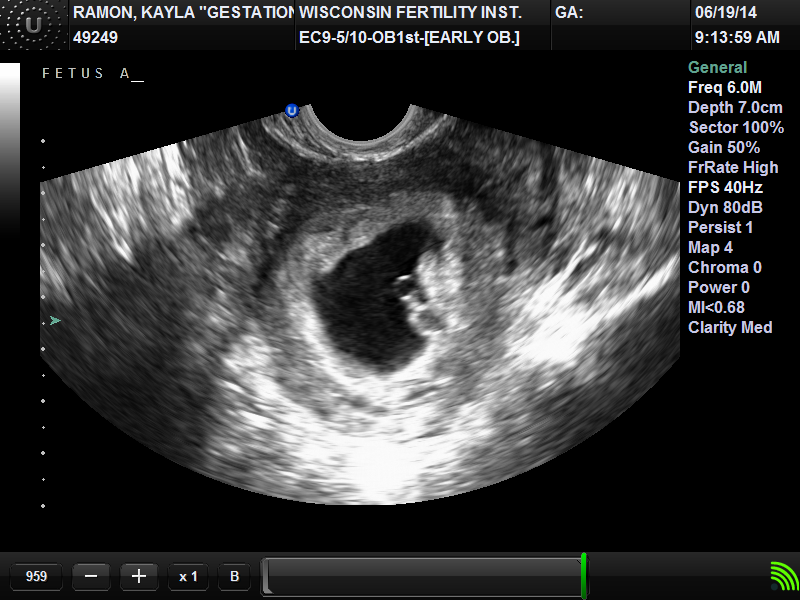

Most of you that are reading this already have heard all of the good news. I am behind on updating I know! The two pictures above are the babies at 6.5 weeks (6/19/14). Sorry the pictures are so small I had to shrink them to fit them on my blog page, they will enlarge if you click on them. At 6.5 weeks I found out I was carrying twins! Baby A was measuring at 6 weeks 4 days with a heart beat of 116. Baby B was measuring at 6 weeks 3 days with a heart beat of 126. Symone went with me to this ultra sound. I had her record the babies heart beats so I could send them to Tom (Intended Father). Tom has wanted twins from the beginning so it was very exciting to tell him he would be having twins. He was extremely happy to hear the good news.